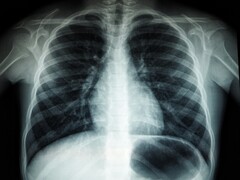

Los investigadores informan de que una sola sesión de peluquería de entre 10 y 20 minutos puede dar lugar a la inhalación de más de 10.000 millones de nanopartículas. Afirman que este nivel de contaminación es comparable al que se produce en medio del denso tráfico de una autopista. Dado el tamaño de estas partículas, pueden penetrar fácilmente en las profundidades de los pulmones. Esto puede provocar problemas de salud como estrés respiratorio, inflamación pulmonar y deterioro cognitivo.